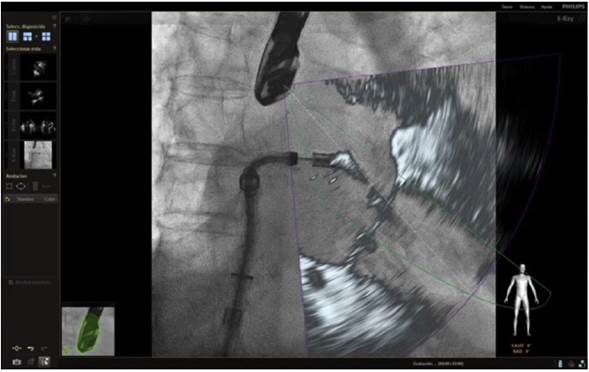

Para procedimientos estructurales cardiacos, más recientemente se desarrolló el uso de imagen de fusión entre tomografía computarizada y fluoroscopia en la cual se utiliza una imagen estática y una dinámica. Esta combinación ofrece una información anatómica adecuada pero no provee imagen en tiempo real y está limitada por el movimiento traslacional del corazón debido a los movimientos respiratorios o cualquier movimiento que el paciente pueda realizar durante el mismo12 (fig. 1).

Figura 1 Imagen de fusión eco 3D/fluoroscopia. Se observa paso de la guía a través de la válvula aórtica, alojándose en el ventrículo izquierdo durante procedimiento de TAVI.